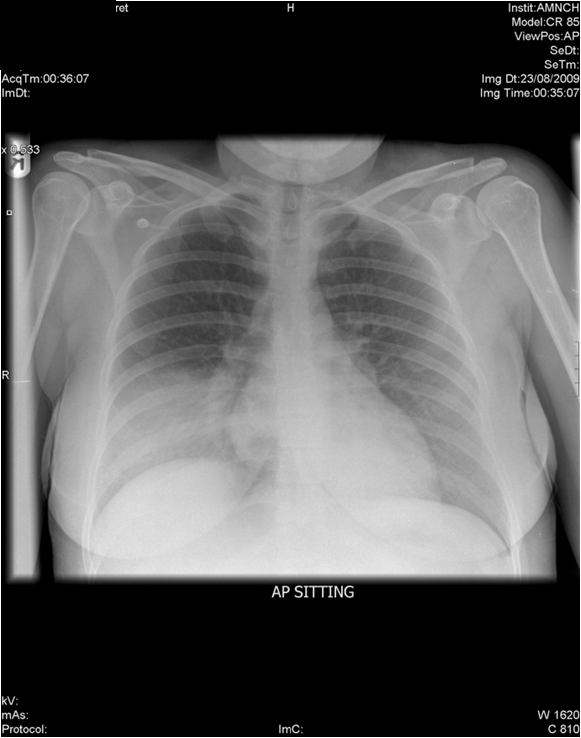

EXAMPLE 4

What do you see? STOP, go through your evaluation before moving on!

What if I told you that this patient is 55 y/o and presented to the emergency room with SOB after slipping on ice and falling on their right side? Does that change your findings?

Diagnosis: This patient has a traumatic right pneumothorax also with fractures of the right 3-8 ribs and displacement of the 5th and 6th ribs. There is also subcutaneous emphysema of the right chest wall.